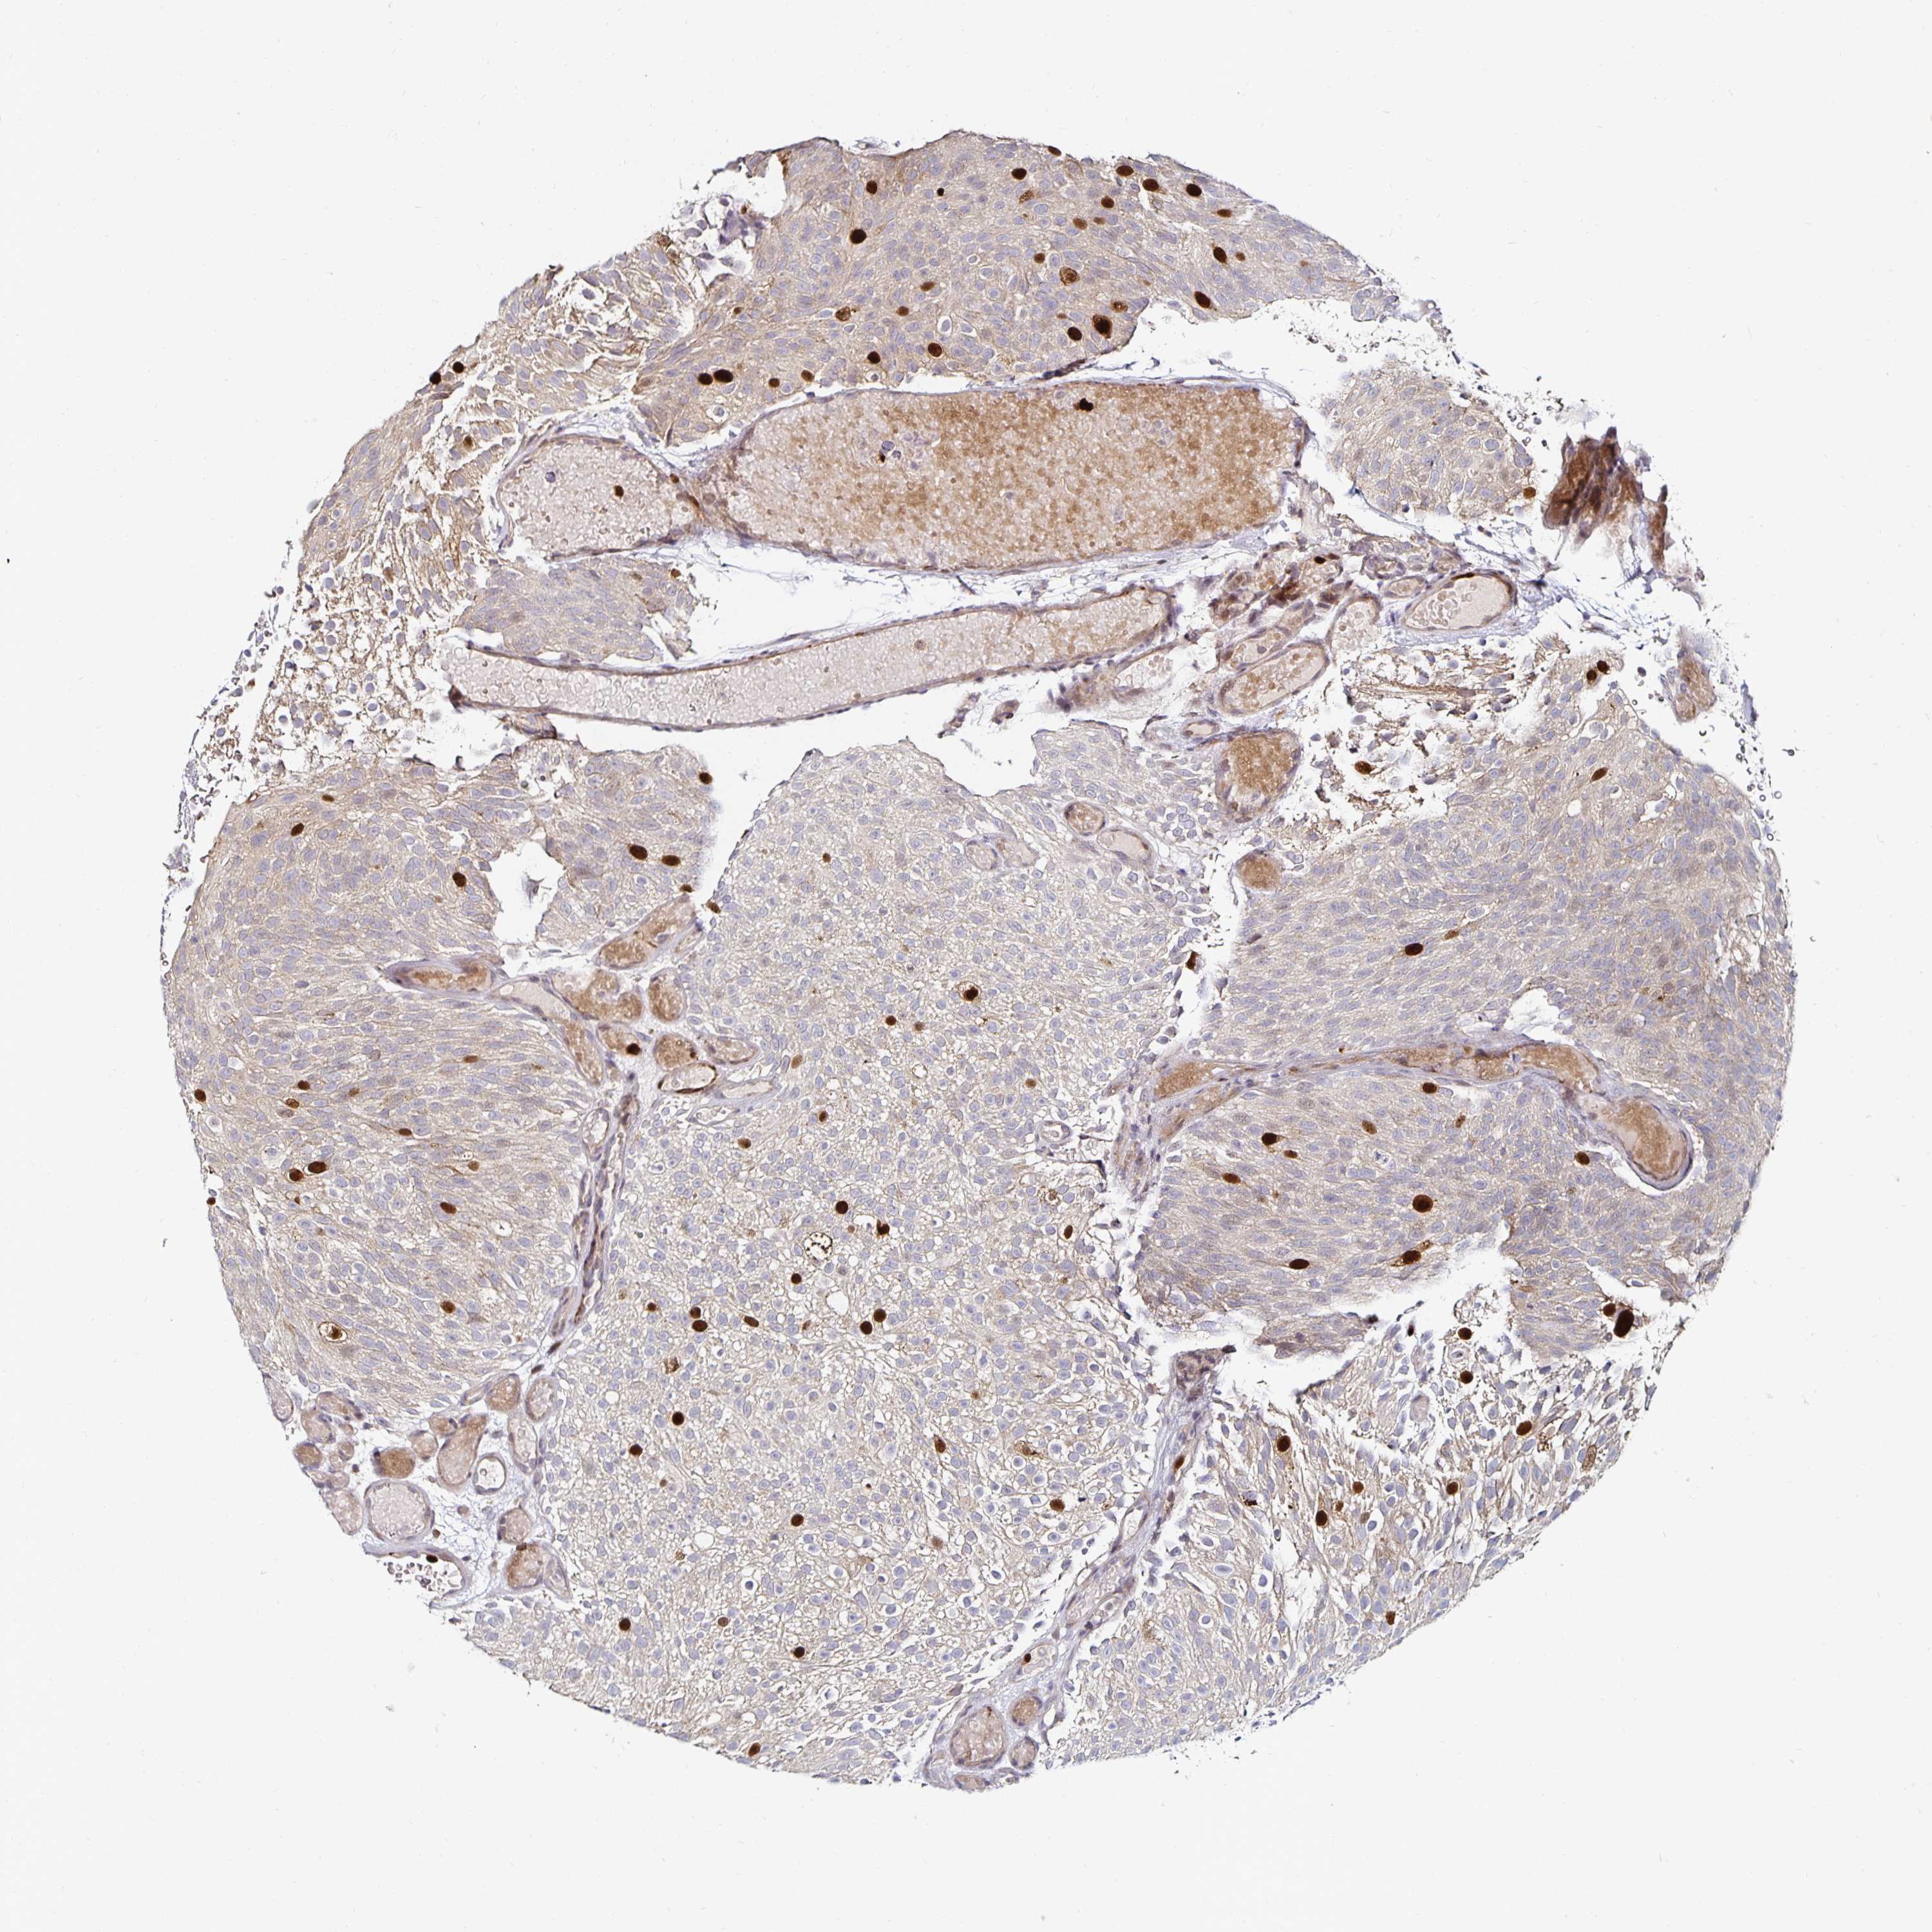

UROTHELIAL CANCER - Protein expressioni

A mouse-over function shows sample information and annotation data. Click on an image to view it in a full screen mode. Samples can be filtered based on level of antibody staining by selecting one or several of the following categories: high, medium, low and not detected. The assay and annotation is described here.

Note that samples used for immunohistochemistry by the Human Protein Atlas do not correspond to samples in the TCGA dataset.

Antibody stainingi

Antibody staining in the annotated cell types in the current human tissue is reported as not detected, low, medium, or high, based on conventional immunohistochemistry profiling in selected tissues. This score is based on the combination of the staining intensity and fraction of stained cells.

Each image is clickable and will lead to virtual microscopy that enables deeper exploration of all samples and also displays staining intensity scores, fraction scores and subcellular localization as well as patient and tissue information for each sample.

HPA005680

HPA050556

CAB033902

CAB062547

CAB068175

Staining

High

Medium

Low

Not detected

Intensity

Strong

Moderate

Weak

Negative

Quantity

>75%

75%-25%

<25%

None

Location

Nuclear

Cytoplasmic/membranous

Cytoplasmic/membranous,nuclear

Urothelial carcinoma, High grade

Urothelial carcinoma, NOS

Urothelial carcinoma, Low grade